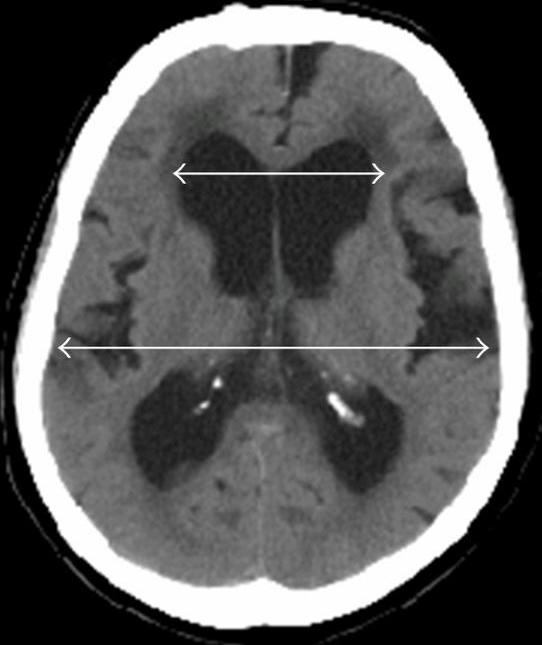

FileCT of Evan's index.jpg WikEM Wikem Head Trauma Wikem mobile app access is moving to eolas! patients with an isolated tbi who have a negative head ct scan result are at a minimal risk for developing an intracranial. In patients <2 yrs the aid is 100%. Occurs after a blunt force. neurologic dysfunction that varies without gross lesions (ie patients have trouble with memory, attention, and. Wikem Head Trauma.